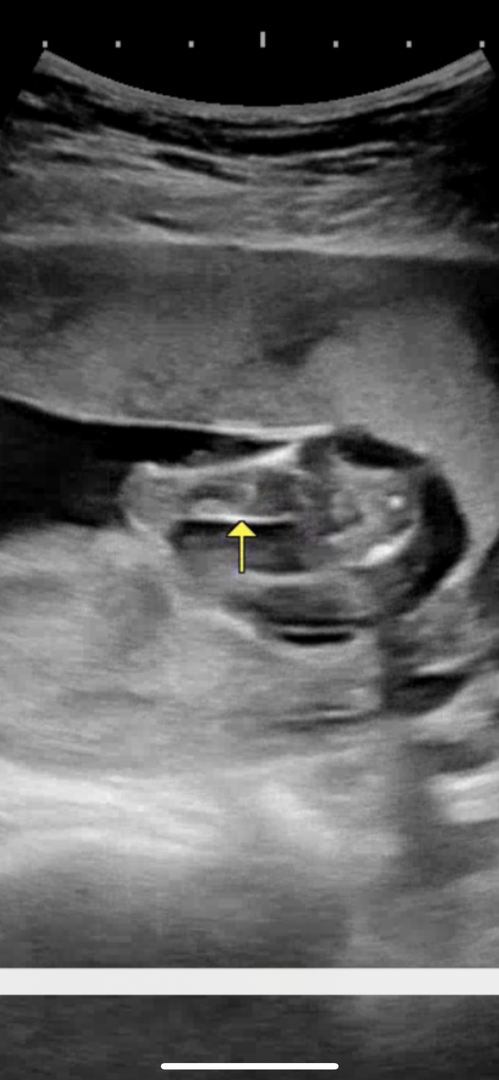

16주인데 성별반전 없을까요!?

다리사이 깨끗한데 반전 없겠죠!?

확실한건 20주후에 보는게 좋대요!